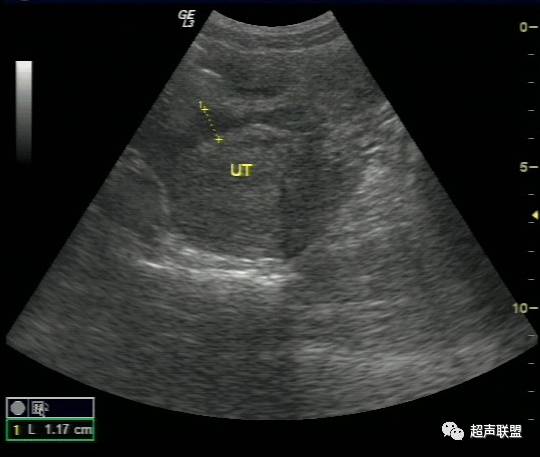

在耻骨联合上方做纵切、横切、斜切观察子宫形态、大小、子宫内膜厚度、宫腔内有无妊娠囊,双侧附件区及盆腔有无明显包块及液性暗区。并观察肝肾间隙、脾肾间隙及腹腔两侧有无液性暗区。

超声检查声像图特点:

(1)子宫增大或轻度增大,子宫内膜不同程度增厚,宫内未见妊娠囊。

宫外孕破裂出血是妇产科最常见的急腹症之一。出血量大者,病情特别危急,需要立即作出诊断和鉴别诊断,以便采取适当而有效的治疗措施。对于一个临床主要表现为下腹剧痛,超声表现为:子宫轻度增大,子宫内膜不同程度增厚,宫内未见妊娠囊;一侧附件区可探及不均质包块,包块形态欠规则,边界不清楚,回声紊乱;陶氏窝可见多少不一不规则的液性暗区,暗区中有密集点状回声。盆腔甚至腹腔积液的妇产科急症患者。检查者应该想到上述疾病。并尽可能详细询问月经史、性生活史及临床病史,结合尿或血HCG检查、血常规检查等,进行综合分析判断。随着超声仪技术的发展,阴道彩色多普勒检查的应用,宫外孕包块内滋养层血流的检测,将更有助于宫外孕破裂的诊断及鉴别诊断。